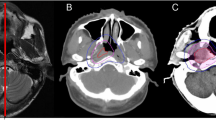

The patient immobilisation, CT simulation and target volume delineation details have been described previously by Zhao [10] and Xiao [13]. The brainstem, spinal cord, optic nerves, optic chiasm, pituitary, temporal lobes, lens, parotids, TMJs and mandible were contoured as organs at risk (OARs).

The target volume prescription doses of the gross tumour volume of the nasopharynx (GTVnx), the gross tumour volume of the involved lymph nodes (GTVnd), clinical target volume 1 (CTV1, the area from 0.5 cm to 1.0 cm outside the GTV that involves the potential sites of local infiltration) and clinical target volume 2 (CTV2, the margin from 0.5 cm to 1.0 cm around CTV1 and the lymph node draining area (Levels II, III, and IV)) were 68 Gy, 60–66 Gy, 60 Gy and 54 Gy, respectively. In total, 30 fractions were administered at 1 fraction daily, 5 days/week. The maximum doses to OARs, which were restricted to prevent exceeding their tolerance doses, were as follows: 56 Gy for the brainstem; 45 Gy for the spinal cord; 60 Gy for the temporal lobes; 5 Gy for the lens; 50 Gy for the optic nerves, chiasm, TMJs, and mandible; and 40 Gy for the parotids. This plan was approved upon meeting the following criteria: (1) the prescribed dose encompassed at least 95% of the target volume, (2) no greater than 1% of the GTVnx could receive ≤93% of the prescribed dose, (3) the maximum dose point was located in the GTVnx, and (4) the isodoses were normalised to the maximum dose, with the chosen prescription isodose for the GTVnx equalling at least 80% of the maximum dose. For the critical organs with functional subunits organised in a series, the dose to 5% of the volume (D5) could not exceed their tolerance doses, and the maximum dose delivered to 1 mL of the cervical segment of spinal cord could not exceed 45 Gy. For the critical organs with functional subunits organised in parallel, the dose constraints to 33% of the volume (D33) were less than their tolerance doses [10,13]. The actual exposure doses of targets and OARs are presented in Table 2.

Late toxicity of the nervous system

In total, 16 patients (7.69%) had late injuries of the nervous system, including 1 (0.48%) with brain stem injury, 6 (2.88%) with cranial nerve damage and 9 (4.33%) with temporal lobe injury (Table 3). Two patients presented grade 4 injuries of post-cranial nerves. Patients with brain injuries exhibited varying degrees of unsteady gait, limb weakness, memory loss and limb numbness. The patient that developed a brain stem injury at 1 year was diagnosed with stage T4 with the GTVnx next to the brain stem. Cranial nerve damage was found in 1, 2, 1 and 2 patients in years 2, 3, 4 and 5 after RT, respectively. Temporal lobe injury was found in 4, 2, 2 and 1 patients in years 2, 3, 4 and 5 after RT, respectively. The distribution of the T stages is shown in Table 4.

The occurrence rate of late injuries in the nervous system after conventional RT in NPC patients was 13.5%-42.8% [2,3,16], the rate of late injuries in the nervous system over grade 3 was 1%-4.5% [3-5]. The stage T3 or T4 NPC patients always required the additional administration of 6–8 Gy to the skull base or to the intracranium. After an irradiation dose of 70 Gy to the nasopharynx, the irradiation dose of the temporal lobes and cranial nerves on both sides of the cavernous sinus reached over 70 Gy, which lead to a greatly increased risk of injury. Of 200 NPC patients with more than 5 years survival after conventional RT, Sumitsawan [3] reported that 7% had brain injuries and 1.5% had severe injuries. Kong’s [2] study showed that late injuries of the spinal cord and of the cranial nerve affected up to 9.8% and 31.8% of patients, respectively, within 5 years after 2-D RT. In our research, 83 patients (40%) were classified as stage T3 or T4. Although the mean irradiation dose of nasopharynx reached 72 Gy, no late spinal injuries occurred, 1 (0.48%) brainstem injury occurred, 6 (2.88%) cranial nerve injuries occurred and 9 (4.33%) temporal lobe injuries occurred. Most patients with temporal lobe injuries were stage T3 or T4 of disease, which might have resulted from the high dose of RT to the temporal lobes because of large tumour invasion to the skull base or to the intracranium. Zhou [17] and Su [18] conducted long-term follow-up studies regarding radiation-induced temporal lobe injury in patients with NPC after IMRT. Both studies showed that the temporal lobe injuries were related to the T stage, which was similar to our results. However, the reported incidence of temporal lobe injury was 16% in Zhou’s study [17] and 15.4% in Su’s study [18], which included 305 and 259 NPC patients, respectively, and 5 years of follow-up. These reported incidence rates were higher than the incidence rates reported in our present study. These results may differ because our study excluded some patients who had recurrence or metastasis; thus, the T3-4 cases were less than 40%. In addition, Zhou’s [17] study showed that the median latency of temporal lobe injury detection in NPC patients after IMRT was 36.85 months with 5 years of follow-up. Moreover, Su’s [18] study showed that the median latency of temporal lobe injury detection in NPC patients after IMRT was 30 months and that the longest latency of temporal lobe necrosis was 56 months. Both studies suggested that the incidence of temporal lobe injury increased gradually over time after IMRT, which was similar to the findings of our study. Although the incidence rates of temporal lobe and cranial nerve damage were relatively low in the present study, the incidence rates increasing year by year in the 5 years of follow-up.

One patient with a grade 2 brainstem injury and stage T4 (cavernous sinus) was included in our study. For this patient, the highest irradiation dose of the brainstem was 54.54 Gy, with a mean dose of 28.79 Gy, which suggested that the injury might have resulted from incidentally high sensitivity of the brainstem to irradiation.